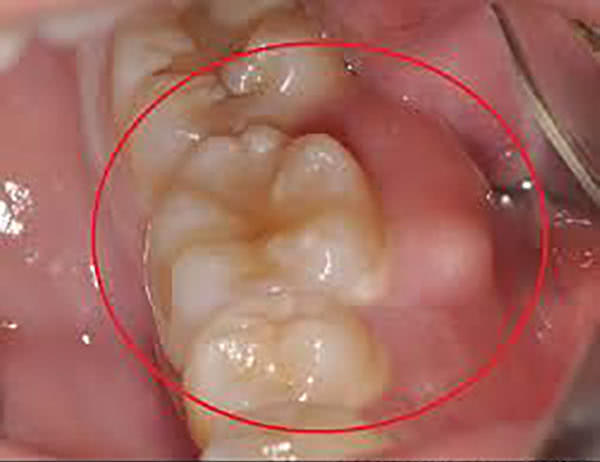

智齿冠周炎

智齿牙冠周围的软组织炎症,主要症状为牙冠周围软组织肿胀疼痛。

阻生智齿生长趋势可能向各个方向倾斜,以向前方倾斜为多见。

人体抵抗力一旦降低,如疲劳、睡眠不足、感冒等,细菌及其毒素会引起牙齿周围软组织发炎智齿冠周炎。

如果治疗不积极的话,有可能形成口腔颌面间隙的感染,所以我们要对这种疾病引起足够的重视才行,一旦发现积极进行治疗。